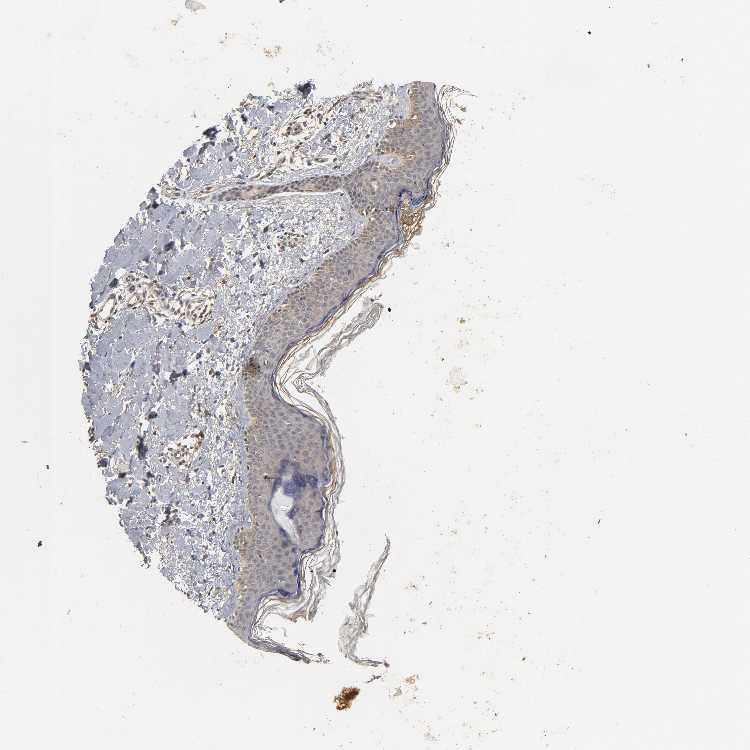

SKIN 2 - Antibody stainingi

Antibody staining in the annotated cell types in the current human tissue is reported as not detected, low, medium, or high, based on conventional immunohistochemistry profiling in selected tissues. This score is based on the combination of the staining intensity and fraction of stained cells.

Each image is clickable and will lead to virtual microscopy that enables deeper exploration of all samples and also displays staining intensity scores, fraction scores and subcellular localization as well as patient and tissue information for each sample.

Antibody HPA019805Antibody HPA020599Antibody CAB004605

Epidermal cells MediumNot detectedMedium